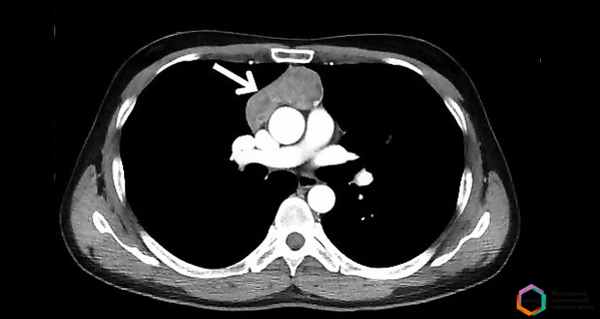

Аксиальный срез. Томограмма на уровне бифуркации трахеи. В переднем средостении достаточно большое патологическое образование, исходящее из вилочковой железы перед восходящей аортой. Это образование не выявляется на обзорных снимках, потому что в прямой проекции контуры средостения определяются анатомическими структурами или патологическими образованиями, которые кондурируются воздухсодержащей легочной тканью. Являются краеобразующими в этом случае.

В этой ситуации верхняя полая вена справа и нисходящая аорта слева формируют контуры средостения. Увидеть такое образование на рентгеновском снимке очень сложно, практически невозможно. Если у этого пациента миастения, то это и есть прямое показание к выполнению компьютерной томографии.

Томографическая картина. Мягкотканой плотности образования. В этом случае однородной структуры, овальной формы, с четкими контурами, расположенными перед восходящей аортой и общим стволом легочной артерии. Типичная характерная картина тимомы, которая, во-первых, нуждается в верификации, во-вторых, в соответствующем хирургическом лечении.